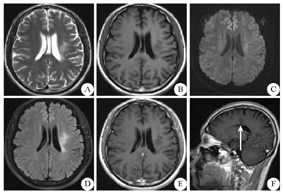

2018年7月31日患者复查颅脑MRI(平扫+强化)显示:左侧基底节区T1WI呈等低信号,T2WI呈等高信号,T2 FLAIR呈高/低信号,DWI呈部分低信号,炎性脱髓鞘病灶较前吸收,范围缩小(图4)。

A~C:平扫;D:DWI;E、F:增强扫描(箭头所示为"煎蛋征");DWI:弥散加权成像